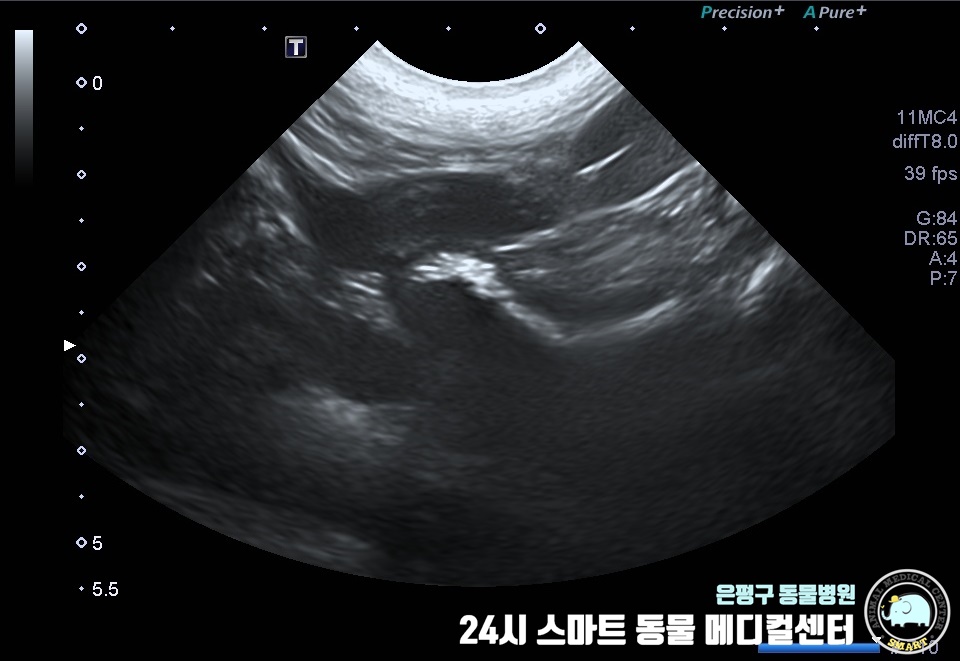

생식기에 황농이 확인되어 자궁경부측의 감염 가능성이 있는 것으로 보이며, 검사 결과 자궁축농증으로 확인되었습니다.

질 주변의 고름이 관찰되었으며 자궁부에서는 약간의 확장과 출혈이 관찰되었습니다.

또한 양쪽 난소 주변에 난소 낭종이 다수 인정되었으므로 항생제 감수성 테스트를 의뢰하여 실시했습니다.